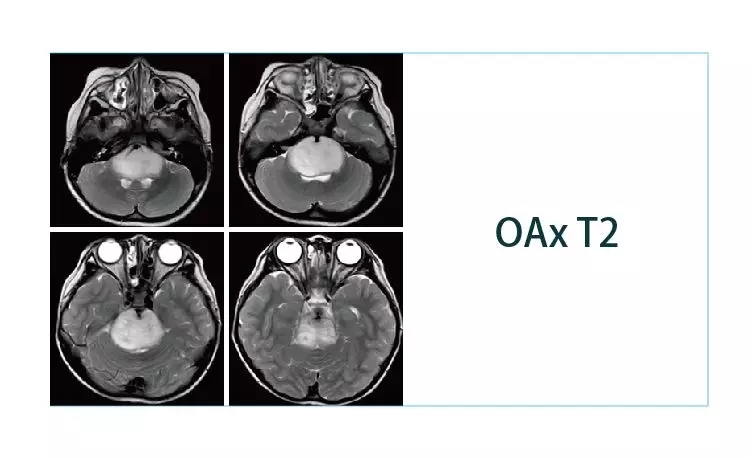

【朗润影像档案】磁共振影像病例分享(编号20190329)

2019-04-01 09:13:05